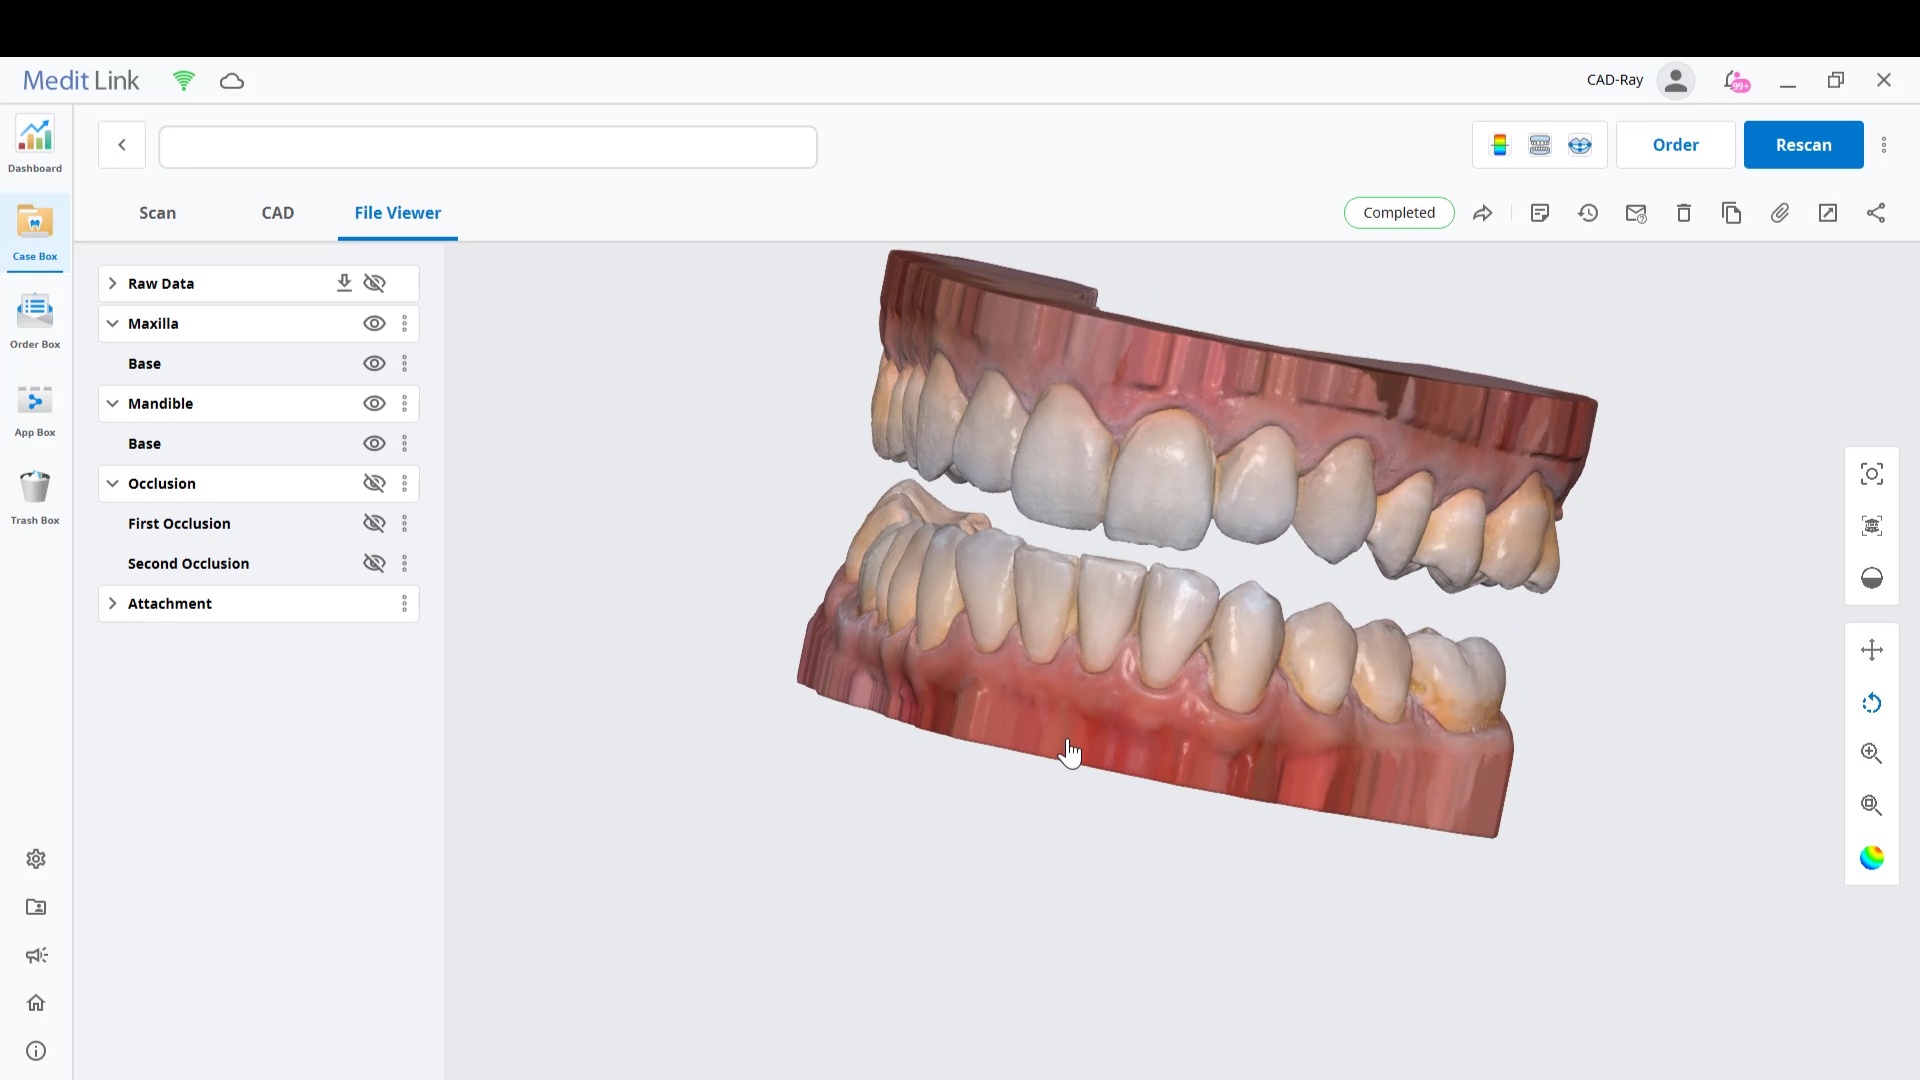

Using the CT as a Remount Jig If You Have Lost The Vertical Dimension For Some Reason or Another

November 20, 2020At CAD-Ray, we have now designed over 20,000 implant cases since 2013. One of the most common requests we get is from doctors doing full arches and their desires to […]